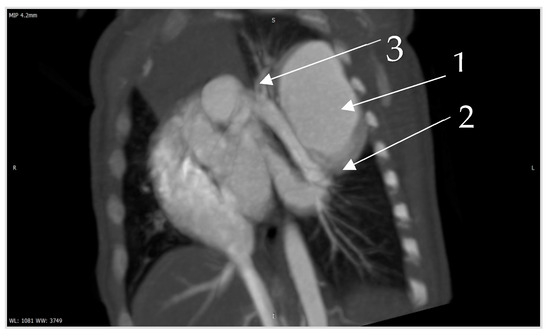

Figure 6. Contrast CT—native image of the branches of the pulmonary artery for three lower and two upper segments. Preoperative diagnostics focus on 3D-CT reconstruction and detailing of the anatomical variations of all arterial and venous vessels, as evident from our case. Contrast CT (Figure 4, Figure 5 and Figure 6) shows communication between the left lower branch of the pulmonary artery—an aneurysmal formation—arrow 1 in Figure 6, measuring 35 × 30 × 25 mm, and drainage into a wide vessel with an irregular shape and through the left inferior pulmonary vein—arrow 2 in Figure 6 into the left atrium—arrow 3 in Figure 6 (independent branching of the subsegmental branches of the LPA for three lower segments and two upper). The inlet and outlet vessels of the AV malformation are shown. The bronchography shows a lack of lung structures in the location of the aneurysmal formation. There are also no signs of pressure and/or hypoplasia in the rest of the left lung.